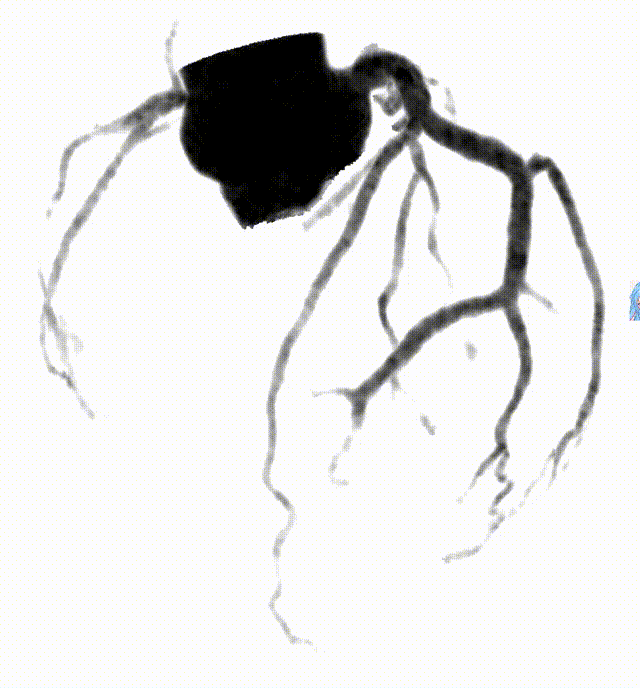

上述二图,皆出自同一人、同一种、同一次检查图像,乃冠脉CTA图像

基于这些突破,uCT SiriuX给我们带来了很多惊喜,文中开头所展示的冠脉CTA生成类DSA、类MR图像功能只是冰山一角,让我们进一步了解该设备在医院的实际临床应用及图像质量。

传统CT通常只能提供单时相静态结构成像,但uCT SiriuX打破了局限,可提供全心动周期多个时相的清晰结构成像信息,动态展示心脏结构运动变化,达到了类DSA、类MR的效果。

如此一来,便可进一步帮助精准测量冠脉狭窄程度、观察狭窄变化及斑块应力变化,进而预测斑块进展与破裂。此外,图像清晰展示瓣膜开合运动,为瓣膜的结构完整性评估和尺寸测量提供可靠依据,具有重要的潜在临床应用价值。

冠脉CTA  VS DSA